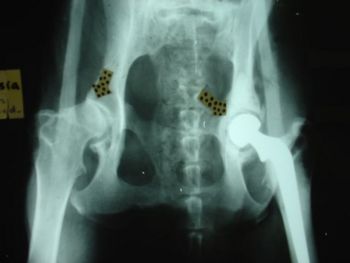

When your pet has suddenly started to change his behaviour, or you notice he appears to be lethargic, it could be that he has a problem with one or more of his joints. Arthritis is not a condition that only appears in a senior dog’s time of life, a puppy can also suffer from arthritis.

However, if your puppy or dog is diagnosed with arthritis there is no need to panic. Your vet will be on hand to guide you. He will help your dog with medicine, and supply valuable information on how to make simple changes to your pet’s lifestyle to keep him comfortable.